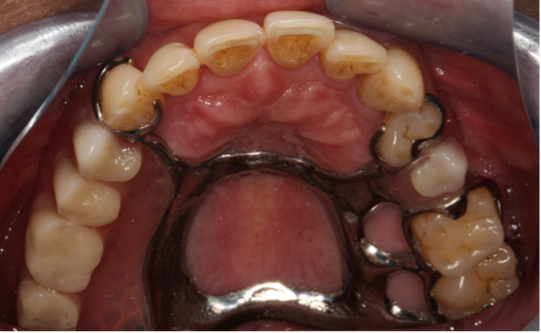

图 活动义齿佩戴图